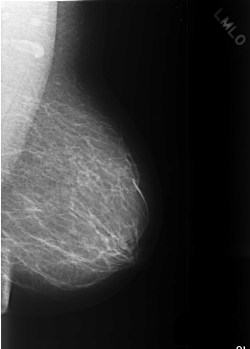

C_0369_1.LEFT_MLO

LEFT_MLO LINES 5576 PIXELS_PER_LINE 4000 BITS_PER_PIXEL 12 RESOLUTION 50 NON_OVERLAY